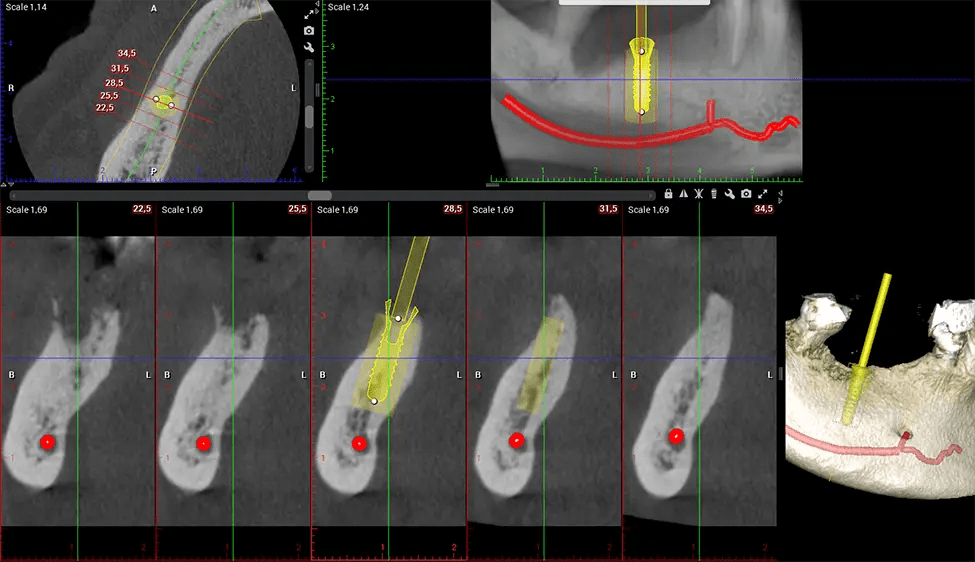

When paired with extractions, dental implant placement, or bone grafting, CBCT technology can provide you with a quicker and much more comfortable experience. This is because the 3D image provides a more detailed picture of your entire oral cavity, allowing your dentist to walk you through each step of the process before it occurs. This often helps patients feel more prepared and comfortable overall, especially if they have had a traumatic experience with past dental treatments.

Planmeca Viso G7 CBCT ( Cone Beam CT Scan ) is designed to surpass the demands of industry leaders, specialists, and large institutions. It’s has a large ø25×30 cm sensor with four built-in cameras. It can capture unlimited volume sizes from a ø3×3 cm to a ø30x30cm volume capturing the skullcap through C7 on the cervical spine. The Planmeca Viso G7 offers the industry’s largest single volume scan of ø30×19 cm. It’s poised to handle advanced imaging modalities such as Planmeca ProFace® and Planmeca 4D™ Jaw Motion technology. The occipital head support allows an unimpeded view of facial tissue.

Our patented SCARA technology enables doctors to capture True Extraoral Bitewings that are as accurate at detecting caries as a 2D bitewing series, but with half the radiation dose. With our bitewings, doctors can view the apices of teeth on both jaws providing a more comprehensive view of the patients’ anatomy.